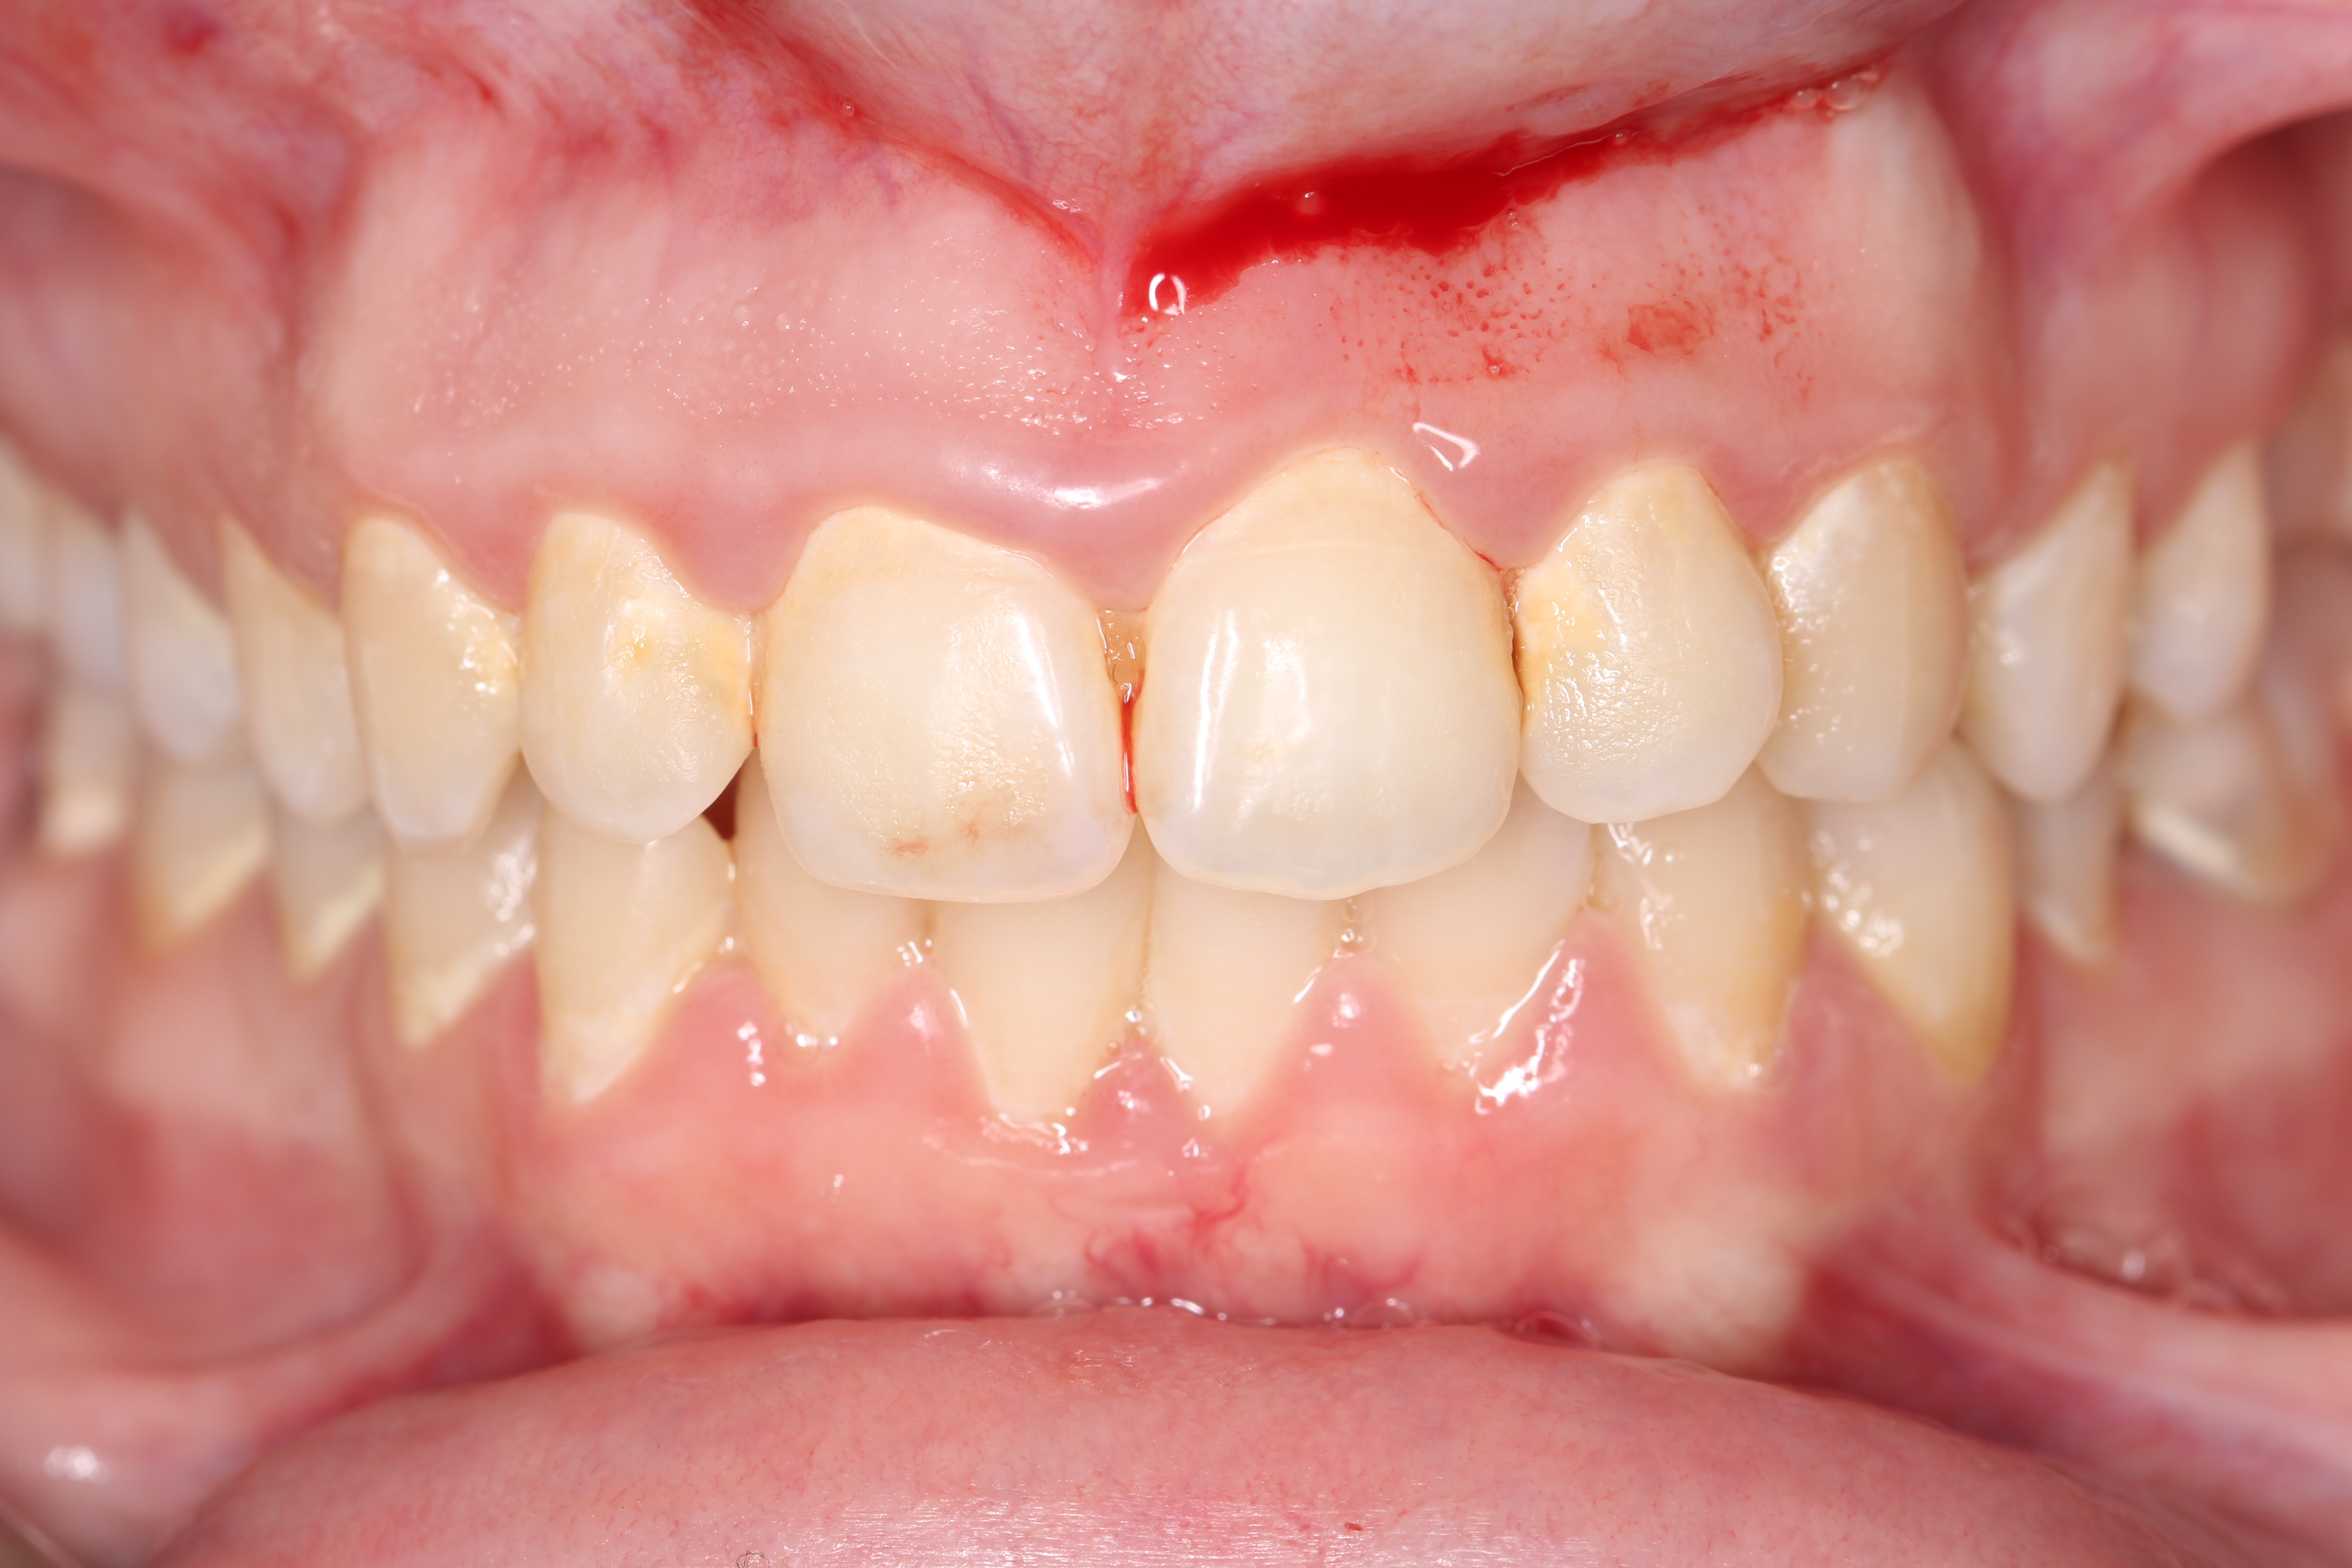

Anterior ceramic crowns and smile design by Mr Stefano Del Monte

From this course, I learned the whole workflow involving designing crowns for an aesthetic case. I learned how to work alongside the lab to create digital smile wax-ups, how to manage patient expectations and prepare teeth quickly and effectively for anterior crowns and veneers.play your timeline of professional development